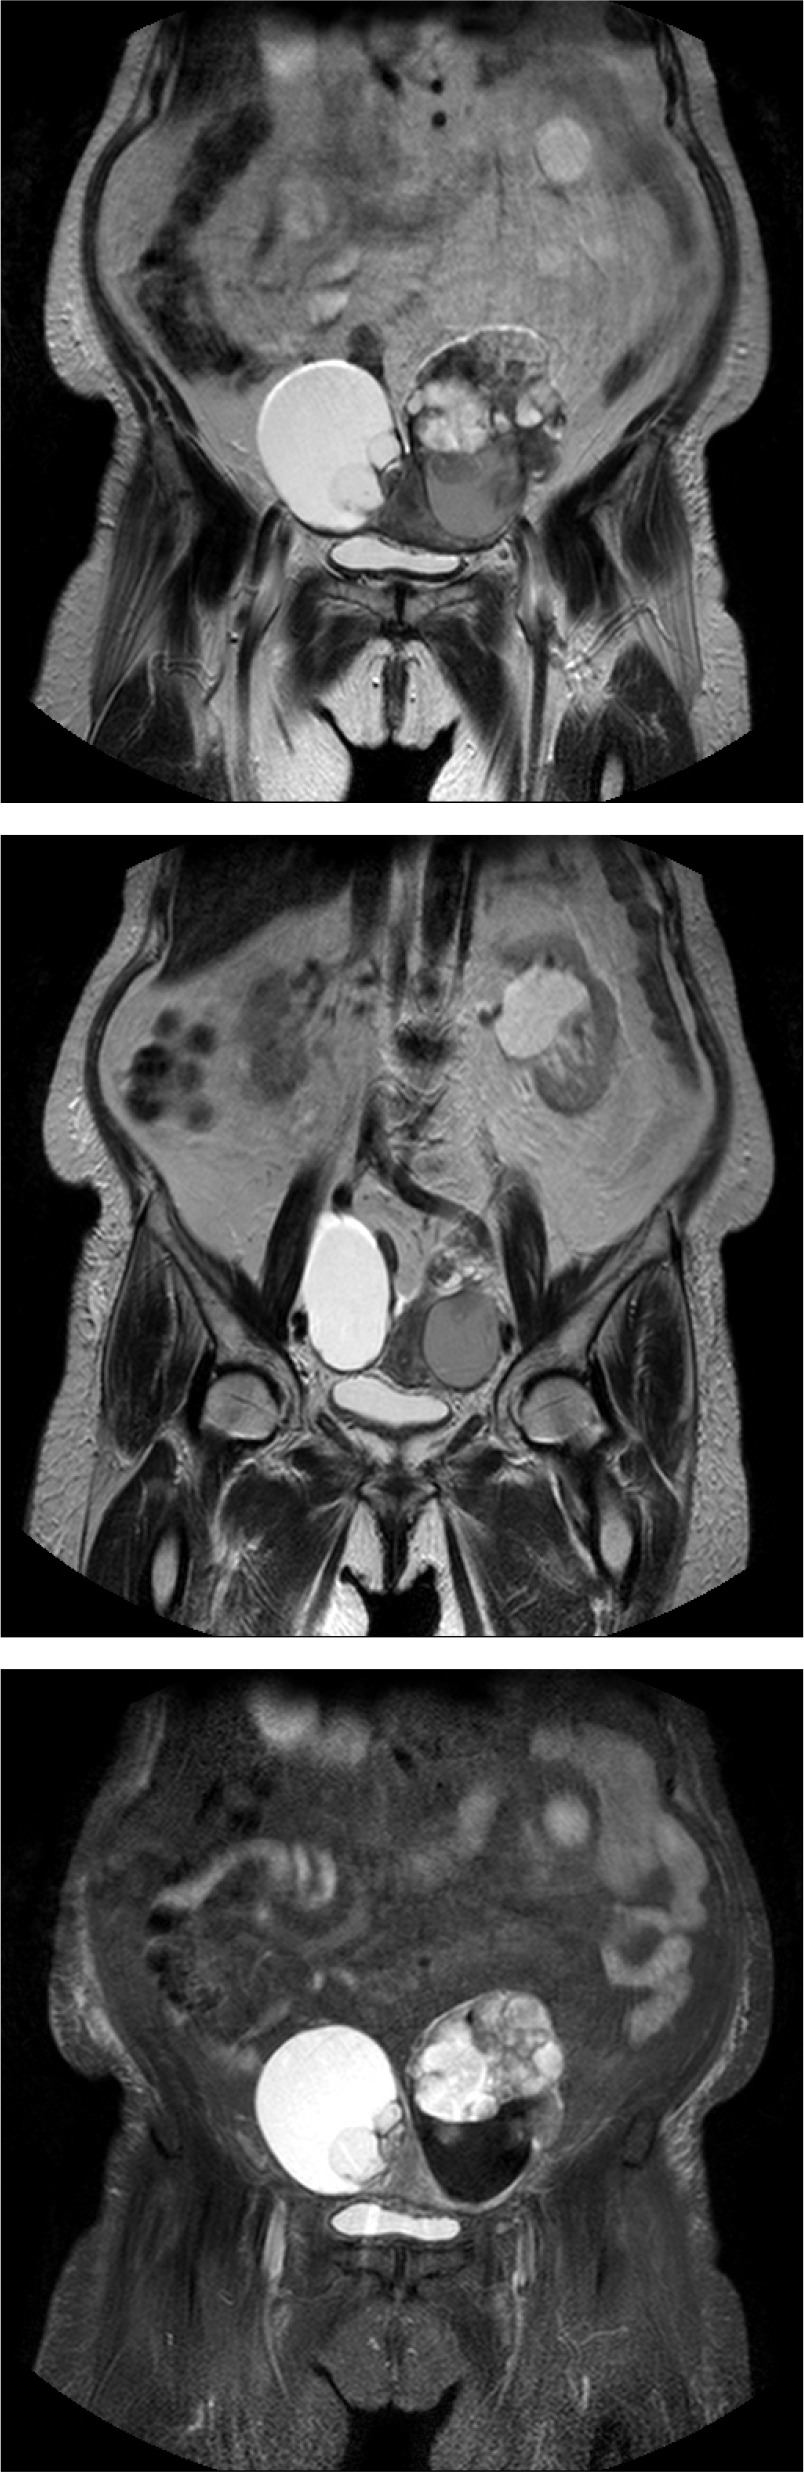

86세의 여성이 배뇨 곤란이 갑자기 심해져서 내원하였다. 환자는 20년 전 요실금 수술을 받은 병력이 있다. 3년 전부터 본원에서 야간뇨와 급박뇨를 치료받던 중 외래 추적 소실 후 3개월 만에 갑자기 발생한 배뇨 곤란 증세로 내원하였다. 신체 검사에서 하복부팽만 및 전신부종소견이 있었다. 초음파검사에서 왼쪽 난소 heterogenous density solid and cystic tumor, 오른쪽 난소에 large cystic tumor 소견이 관찰되었다. 골반 CT를 시행하였고 both ovaries malignancy Krukenberg tumors, 10 cm in each sides secondary stomach tumor 소견이 관찰되었다. 환자는 대학병원으로 전원되었으나 3개월후 사망하였다.

크루켄버그 종양(Krukenberg tumor)은 대개 소화기관에서 기원한 종양이 난소로 전이되는 난소의 전이성 종양으로, 전체 난소 종양의 1∼3%정도를 차지하는 것으로 알려져 있다. 본 케이스는 소화기관, 위암이 난소로 전이된 상태였다. 크루켄버그 종양은 점액 변성과 반지세포(signet ring cell)가 특징적이고 대부분 양쪽 난소 모두 침범된다. 원발암이 진행된 다음에 발견되기 때문에(위암 4기) 크루켄버그 종양이 발견된 지 약 1년 이내에 대부분의 환자가 사망한다. 크루켄버그 종양은 산부인과에서도 희귀한 증례이며, 특히 본 증례는 배뇨증상이 환자의 주 호소 증상이었던 크루켄버그 종양이라는 점에서 의의를 찾을 수 있다.